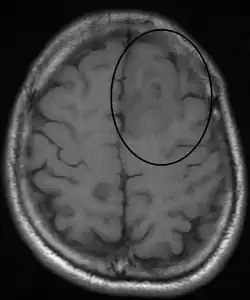

An oligodendroglioma as seen on MRI

Oligodendroglioma arise mainly in the frontal lobe and in 50–80% of cases, the first symptom is the onset of seizure activity without any prior symptoms .[3] Headaches associated with increased intracranial pressure are also common in individuals with oligodendroglioma. Depending on the location of the tumor, many different neurological and neuropsychological deficits can be induced, including, but not limited to, visual loss, motor weakness, cognitive decline, and anxiety.[4] A computed tomography (CT) or magnetic resonance imaging (MRI) scan is necessary to characterize tumor size, location, and hetero- or homogeneity. Final diagnosis relies on biopsy and histopathologic examination of the tumor mass.[3]